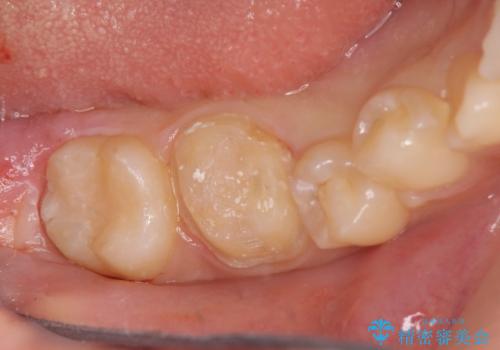

奥歯の高さがない 歯周外科処置で解決 (クラウンレングスニング)

- 奥歯のかけおよび、虫歯の治療を行いました。

右下6番はかけの程度が大きく、詰め物ですと金属でないと難しいとお伝えしました(アンレー)。

金属ではなく、白い修復物を希望されたため、セラミッククラウンで治療することにしました。

その際、舌側の歯の高さがなく歯肉に埋もれ気味だったっため、奥の親知らずをぬくついでに予め歯周外科処置(要は歯の周りの組織の手術という意味です)を行い、歯ぐきの高さを下げました。